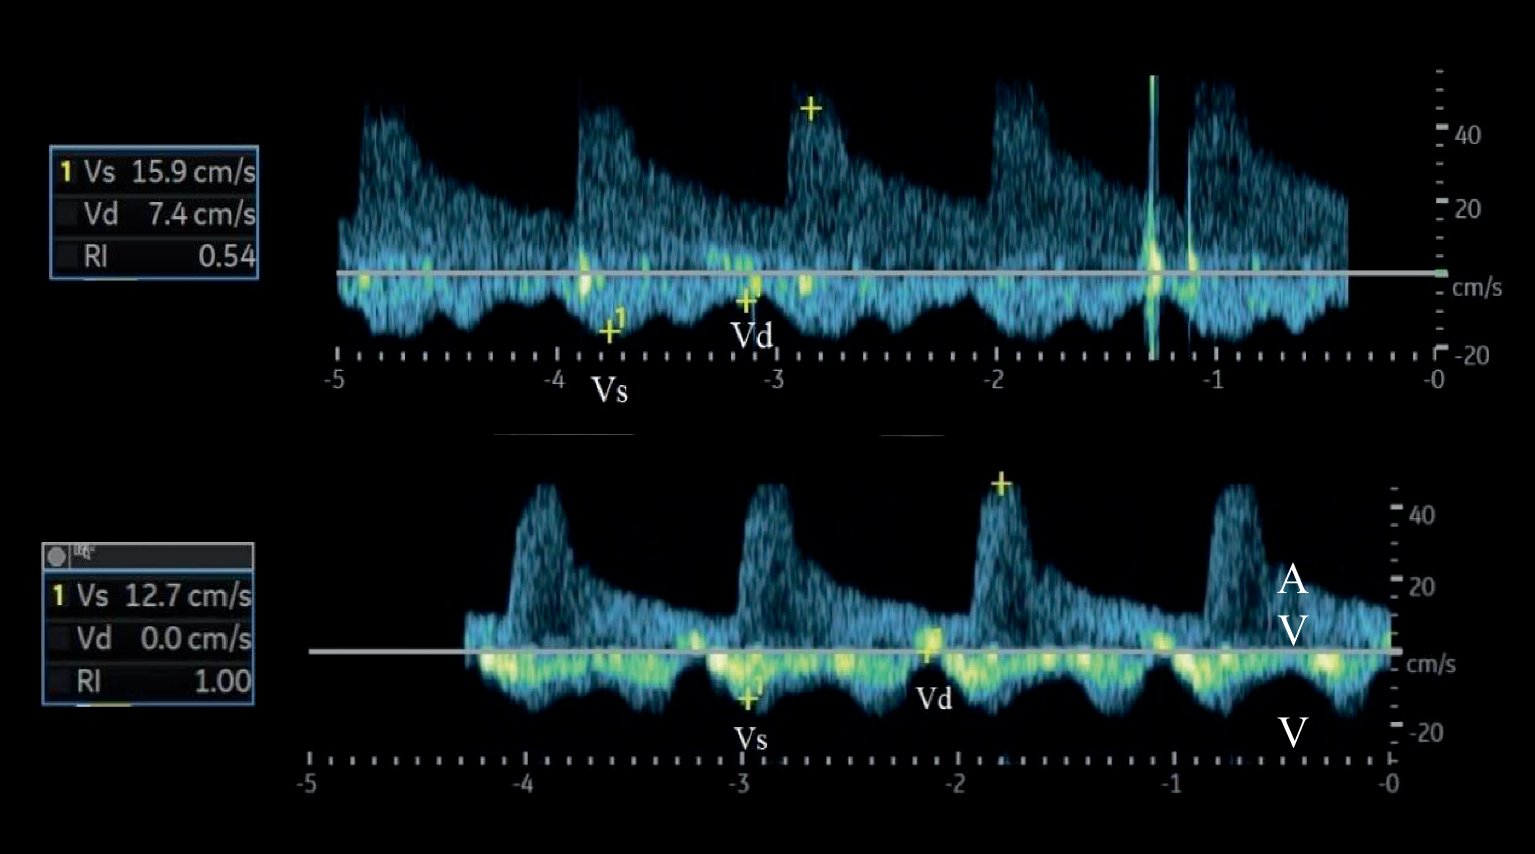

Andere quantitative Messgrößen sind der Index der venösen Impedanz (Venous Impedance Index [VII]) und der Index der renalvenösen Stase (Renal Venous Stasis Index [RVSI]). Der VII berechnet sich nach folgender Formel: VII = (maximale systolische Flussgeschwindigkeit Vs − enddiastolische Flussgeschwindigkeit Vd)/maximale systolische Flussgeschwindigkeit Vs. Bei einem kontinuierlichen Flussprofil nimmt der VII einen Wert < 1 an; mit zunehmendem Grad der Kongestion nähert er sich dem Wert 1 an (Abb. 3). Der RVSI gibt den Anteil des Herzzyklus an, in dem kein renalvenöser Abfluss vorhanden ist (Abb. 4). Der RVSI berechnet sich nach folgender Formel: RVSI = (Herzzykluszeit − venöse Flusszeit)/Herzzykluszeit. Er kann einen Wert von 0 bis 1 annehmen, wobei ein höherer Wert einen höheren Grad der Kongestion anzeigt. Ein hoher RVSI korreliert mit dem rechtsatrialen Druck, dem Durchmesser der unteren Hohlvene sowie der Rate kardialer Ereignisse [15]. Das Erfassen kongestiver (doppler-)sonographischer Veränderungen in den abdominellen Gefäßen (VCI, Pfortader, Lebervenen, Nierenvenen) wurde auch unter dem Begriff VEnous excess UltraSound (VExUS) zusammengefasst [16]. Es sollte berücksichtigt werden, dass Patienten mit HI, selbst im scheinbar stabilen Zustand, häufig (30–40 %) dopplersonographische Zeichen einer renalvenösen Kongestion aufweisen können [17]. Zudem zeigen bis zu 40 % der Patienten, die wegen akuter dekompensierter HI aufgenommen wurden, klinische Anzeichen einer residualen Kongestion zum Zeitpunkt der Entlassung, was mit einem höheren Risiko für Mortalität und Wiederaufnahme verbunden ist [18].

Abb. 3

Berechnung des VII (in der Abbildung als RI bezeichnet) mithilfe der venösen Flusskurve bei einem kontinuierlichen (oben) und einem pulsatilen Flussprofil (unten). VII = (Vs−Vd)/Vs. A arterieller Fluss, V venöser Fluss, Vd enddiastolische Flussgeschwindigkeit, VII Venous Impedance Index (Index der venösen Impedanz), Vs maximale systolische Flussgeschwindigkeit. (Modifiziert nach [57])